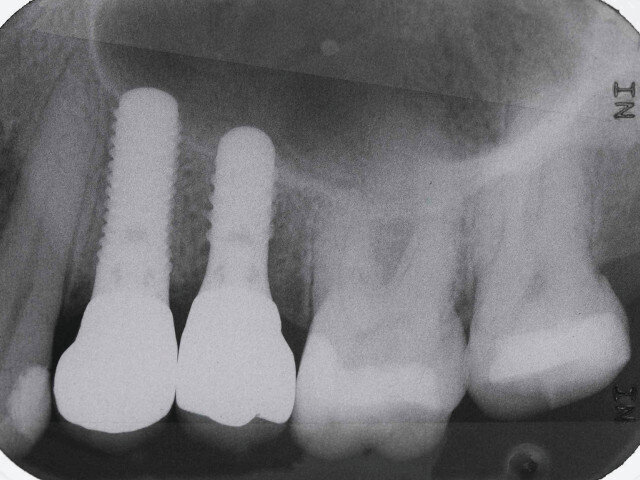

To assist the process, the mounting of a patient’s diagnostic casts remains an important step, as it allows the assessment of critical factors such as occlusion, implant position and forces direction.[2] It also allows exploration into prosthetic options,[2] such as angled abutments (Fig. 1).

Fig. 1: Implant treatment planning

Fig. 14: Implant radiograph

The VF also records the maxillo-mandibular relationship vital to correct mounting, enabling the accurate mounting of complex implant cases (Fig. 13). With exact mounting, the proper position and angulation of dental implants can be achieved.

The use of cone-beam computer tomography remains the gold standard of dental implant treatment planning.[6] However, many clinicians have barriers to the technology either from limited finances, physical access or intimidation. Many implant cases are planned and delivered with little to no clinical records, other than final impressions. The Virtual Facebow provides a digital companion that is accessible, affordable and understandable.